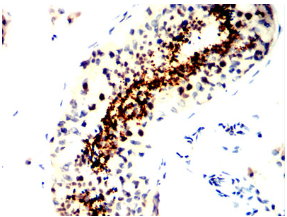

| AC3563 | SPATA19 Mouse Monoclonal antibody[4A9F9] | 100ug | $367 | 10days |

| AC3563 | SPATA19 Mouse Monoclonal antibody[4A9F9] | 200ug | $660.6 | 10days |